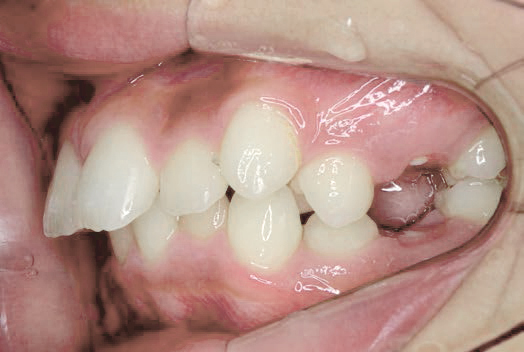

出っ歯

他院で「抜歯して5年かかる」と言われましたが、非抜歯、1年で治りました

Sさん (矯正開始時:12歳)

Before

After

下の奥歯が内側に傾いて、舌の位置が悪く、鼻がつまって口呼吸の状態でした。扁桃腺がよく腫れ、風邪をひきやすく、いびきもあるようでした。

治療を終えて

装置で上あごを拡大し、下の歯の位置を整え、前歯の並びを整えました。お口のトレーニングの効果で鼻詰まりと、いびきも改善。たった1年でこの変化が見られました。もちろん歯は1本も抜いていません。

主訴・治療内容 他院にて「抜歯した上で、ワイヤーを付け、5年かけて治療する」と言われ、他の方法はないのかとネットで調べたところ、当院を知り無料相談に来院されました。

治療期間 1年

費用 462,000円(税込)